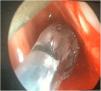

Paciente de 49 años (IMC 29,4 kg/m2 y ASA III) con estenosis subglótica (ES) de más de 70% (grado III) intervenida mediante resección láser y posterior dilatación. Durante la resección láser se empleó ventilación controlada por flujo utilizando el respirador Evone®, que permite controlar todo el ciclo respiratorio regulando tanto el flujo inspiratorio como el espiratorio sin comprometer el intercambio gaseoso a pesar de administrar FIO2 máxima de 0,3 por riesgo de ignición. Antes de proceder a la dilatación endoscópica, se retiró el tubo endotraqueal láser de 4,5 mm de diámetro interno y se inició terapia con gafas nasales de alto flujo (GNAF) para prolongar la oxigenación apneica. El tiempo total de apnea fue de 11 minutos, manteniendo en todo momento SpO2 > 98% y End Tidal de CO2 máximo de 60 mmHg.

A 49-year old patient (BMI 29.4 kg/m2 and ASA III) with grade III subglottic stenosis (> ventilator in flow controlled ventilation mode, which allowed us to regulate both inspiratory and expiratory flow without compromising gas exchange despite maintaining peak FIO2 at 0.3 due to the risk of ignition. Before proceeding with endoscopic dilation, the 4.5 mm laser endotracheal tube was withdrawn and high flow nasal cannula oxygenation was started in order to prolong apnoeic oxygenation. Total apnoea time was 11 minutes, maintaining SpO2 > 70%) underwent laser resection followed by dilation. During resection he was ventilated by the Evone > ventilator; high flow nasal cannula therapy; apnoeic oxygenation-98% and peak EtCO2 60 mmHg throughout the procedure.